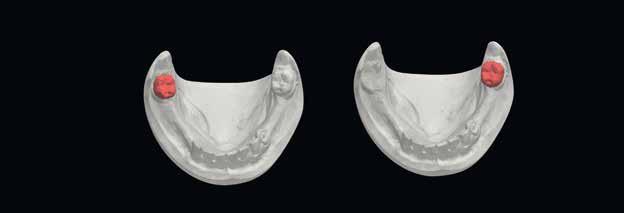

A felső és az alsó állkapocsról történt szituációs lenyomatokat kiöntötték, a laboratóriumi szkennerrel digitalizálták (3Shape), és az adatokat a Digital Denture szoftverbe importálták. A szoftver SR IvoBase® CAD és SR Vivodent® CAD Multi kombinációjával - fogszínű korongokkal - lehetővé teszi digitális protézisek automatizált gyártását.

Ideiglenes protézis CAD-konstrukcióban

Az ideiglenes fogsor elkészítéséhez a még meglévő fogakat törölni kellett a virtuális modellről (3. ábra). Ehhez a szoftver megfelelő eszközöket biztosít. A modellanalízis közben a szoftver lépésről lépésre vezet minket. Az anatómiai jellemzőket megjelöljük és a fogsor kiterjesztésének paramétereit rögzítjük (4. ábra). Az állkapocsviszony meghatározása alapján a függőlegest 5,5 mm-rel megemeltük (5. a ábra). A Digital Denture Full Arch könyvtár segítségével megtörtént a megfelelő fogforma kiválasztása (Phonares® II B71-L50-N3)

(5. b ábra)